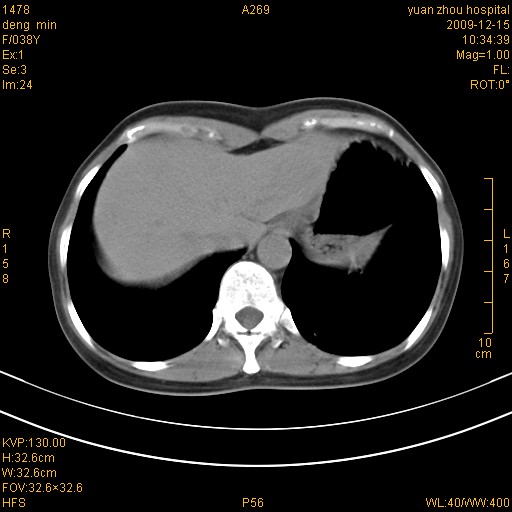

标题: CT23919:F38Y 咳嗽月余 [打印本页]

标题: CT23919:F38Y 咳嗽月余

右肺中下叶、左肺上叶舌段及左肺下叶支气管扩张合并感染。